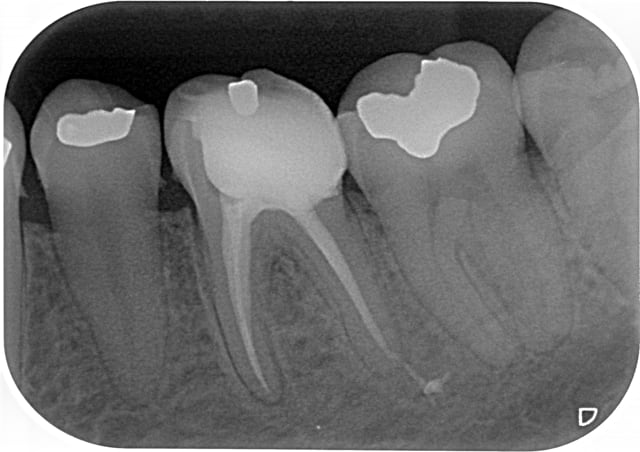

petit jeu:

A vous de trouver quelle endo a été faite au thermafill et laquelle au gutta condensor?

Endo 2 : Thermafil

En général le thermafil est moins radioopaque que la gutta thermocondensée, donc j'aurais plutôt dit la 1, mais c'est vrai que sur la 2 tu as probablement quatre canaux, ce qui augmente la densité et les bouts font un peu "pointu" laissant penser que les tuteurs se sont peut être un peu décalés...

Allez je joue:) sans être sure,mais je dirais

1/Thermafill( on croit apercevoir les tuteurs)

2/gutta condensor ,( je crois voir une spirale dans l' un des canaux mesiaux! )

1:thermafill

Et bien je vois que tout le monde n'est pas d'accord...

endo1 a été fait au gutta condensor

endo 2 au thermafil.

Seul Marc a eu du nez la dessus. ;-)

Comme quoi, radiologiquement, difficile de faire le distinguo entre ces deux méthodes.

C'est la rectitude de l'obturation dans le dernier millimètre apical, surtout sur le canal distal qui m'a mis sur la voie.

Image 1 thermo condensation.

La compression de la technique a provoqué la fusée au niveau de la racine distale de 36.

image 2 thermafil

Je crois apercevoir la pointe du tuteur thermafil sur racine distale de 46.